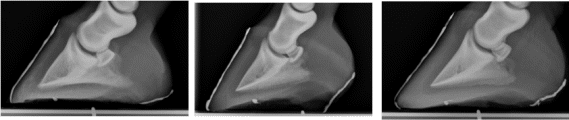

[Fig 2 above] Lateral radiographs above of a laminitis case that was treated with the hoof rehabilitation system. Note the increase in heel depth over the 5 month treatment period. This change is a consistent finding in horses undergoing this method of hoof rehabilitation, although it has never been proven possible.

Foot 1 Foot 2 Foot 3